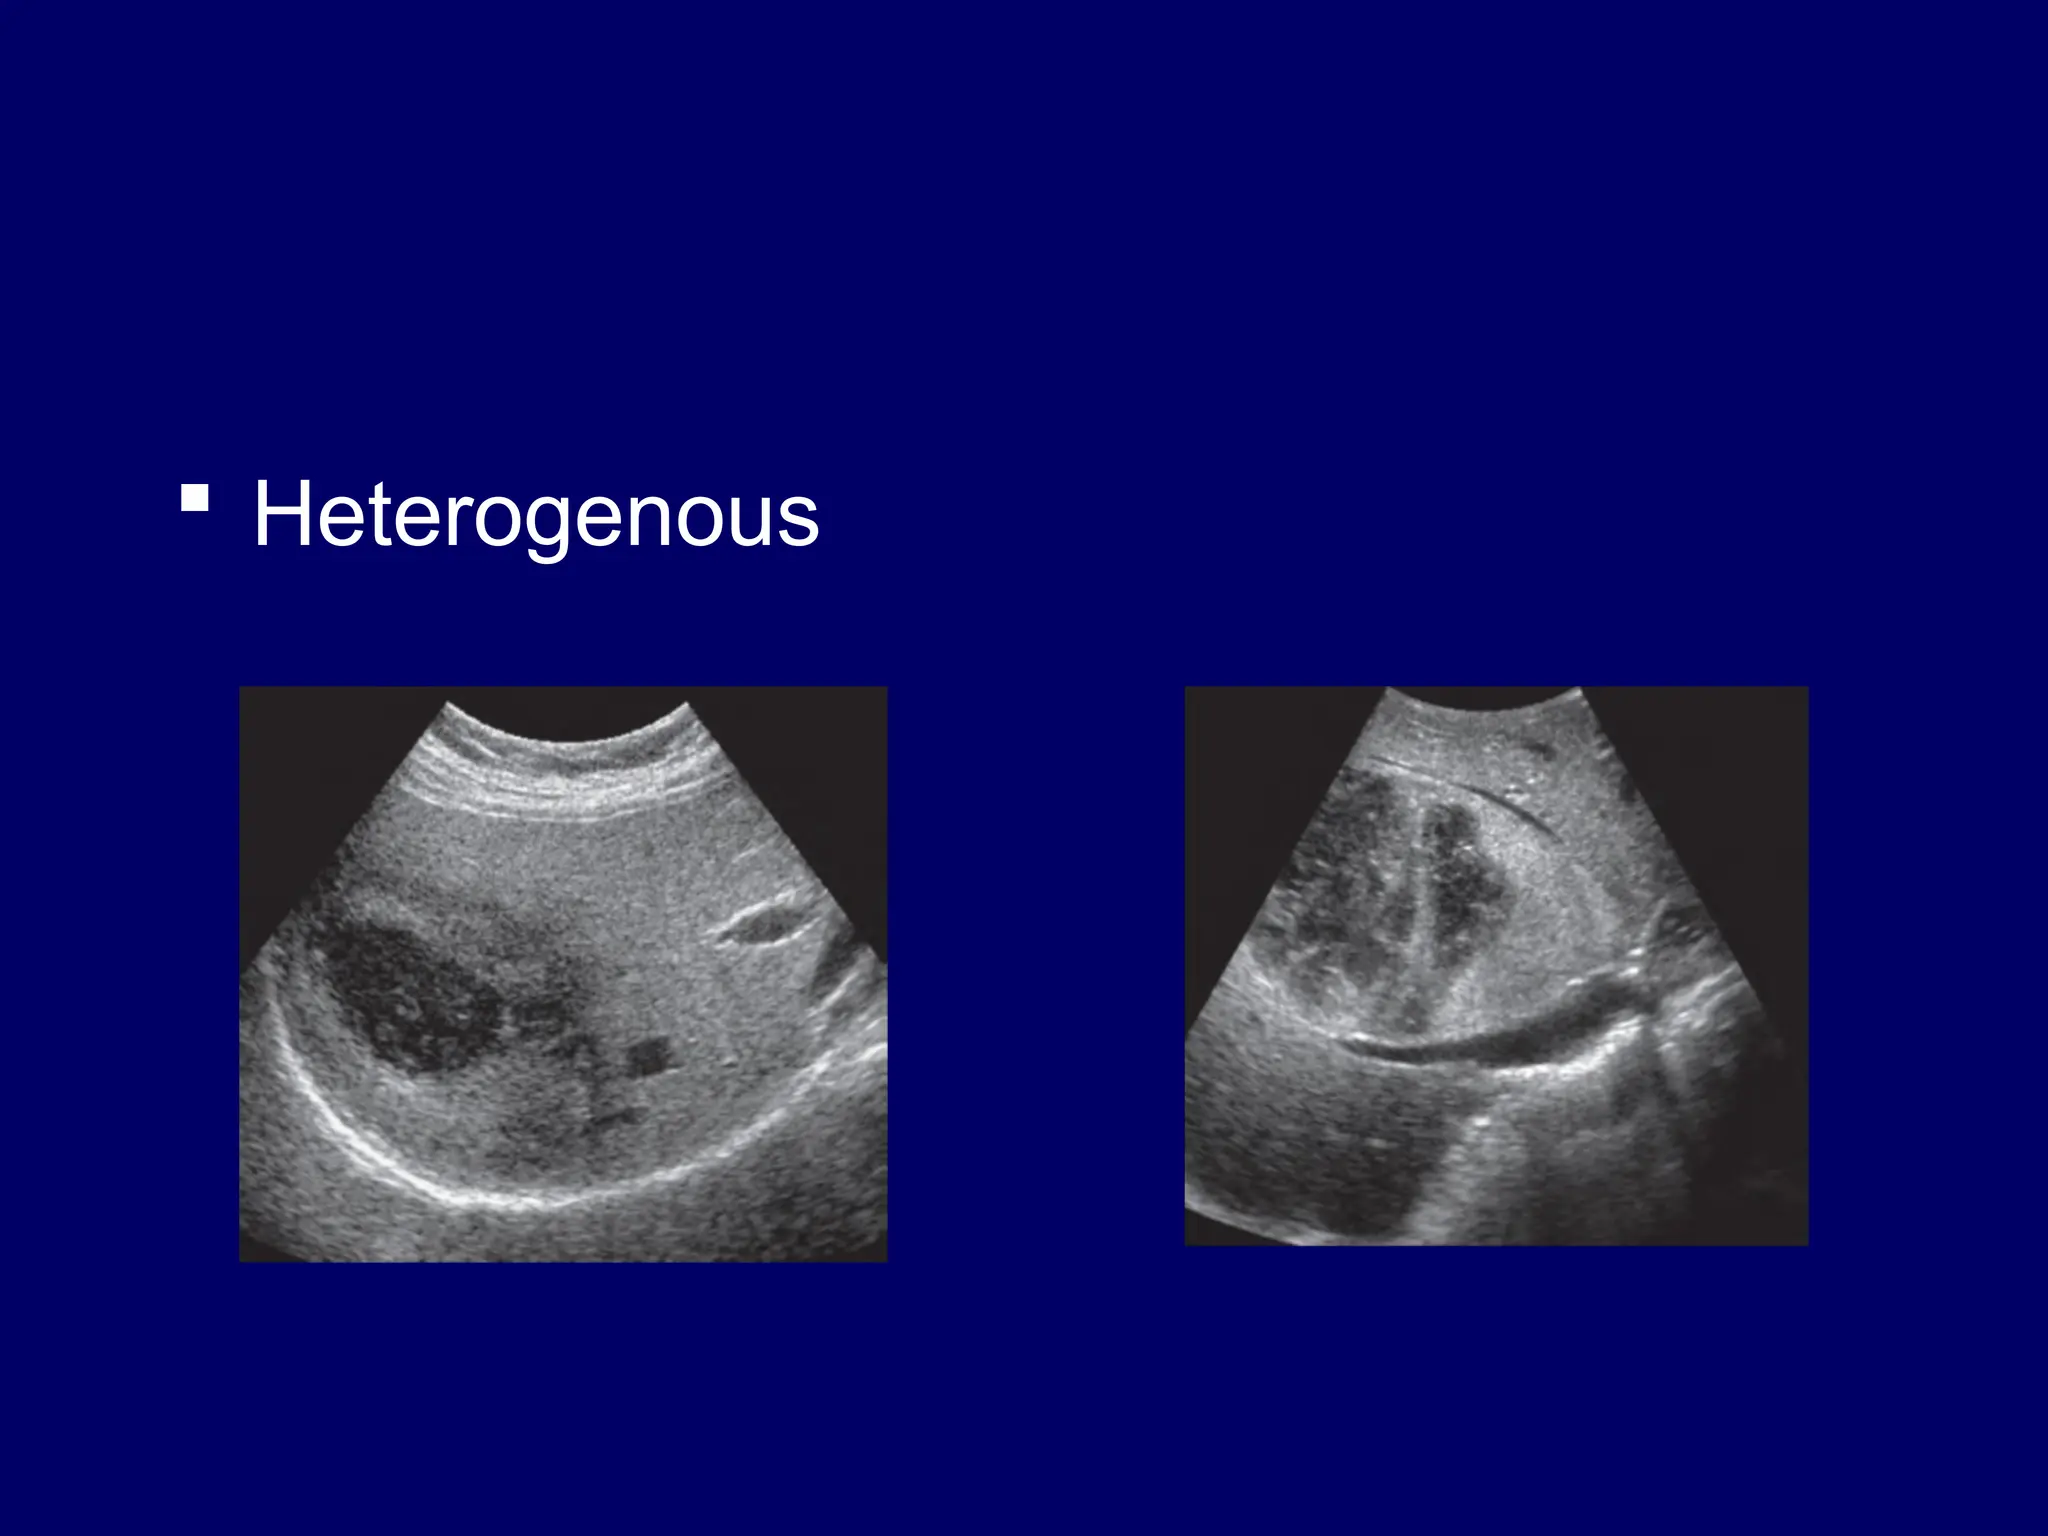

 Heterogenous

Interpretation  Shadowing andthrough transmission – Acoustic shadowing – Acoustic enhancement – Edge shadowing  Echogenicity – Anaechoic…….black – Hypoechoic …..falls in btn black n white – Hyperechoic--white